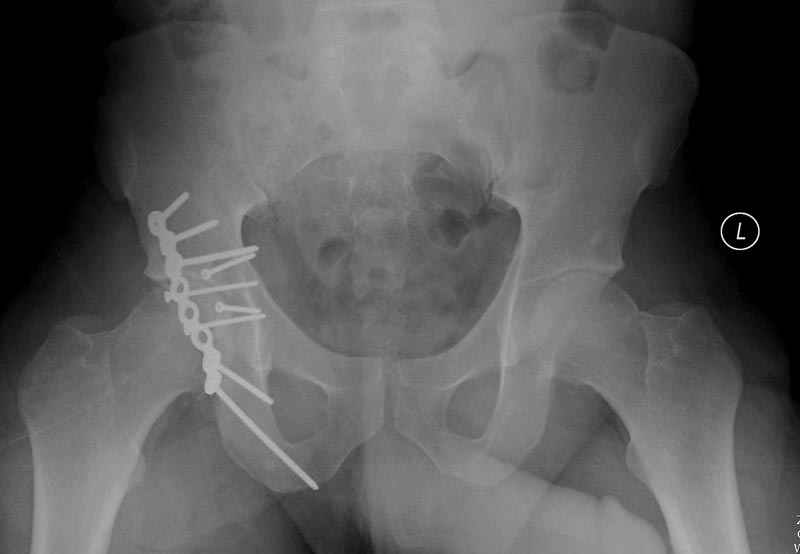

5:24 Рентгенограмма таза, вызывают врача ортопеда (снимок N1), его диагноз: закрытый переломо-вывих правого тазабедренного сустава, получает добро на закрытую репозицию в приемном отделении

сустава, репозиция вывиха (N4), фиксация фрагмента 2.7(4) мм шурупами и допольнительно реконструктивной пластиной на 8 дырок, фиксация 3.5мм шурупами проксимально и дистально.

Интраоперционные N5 косая запирательная и N6 подвздошный снимок

11:50 больной в послеоперационной, рентгенограмма N7, компьютерная томограмма в тот же день N8-10